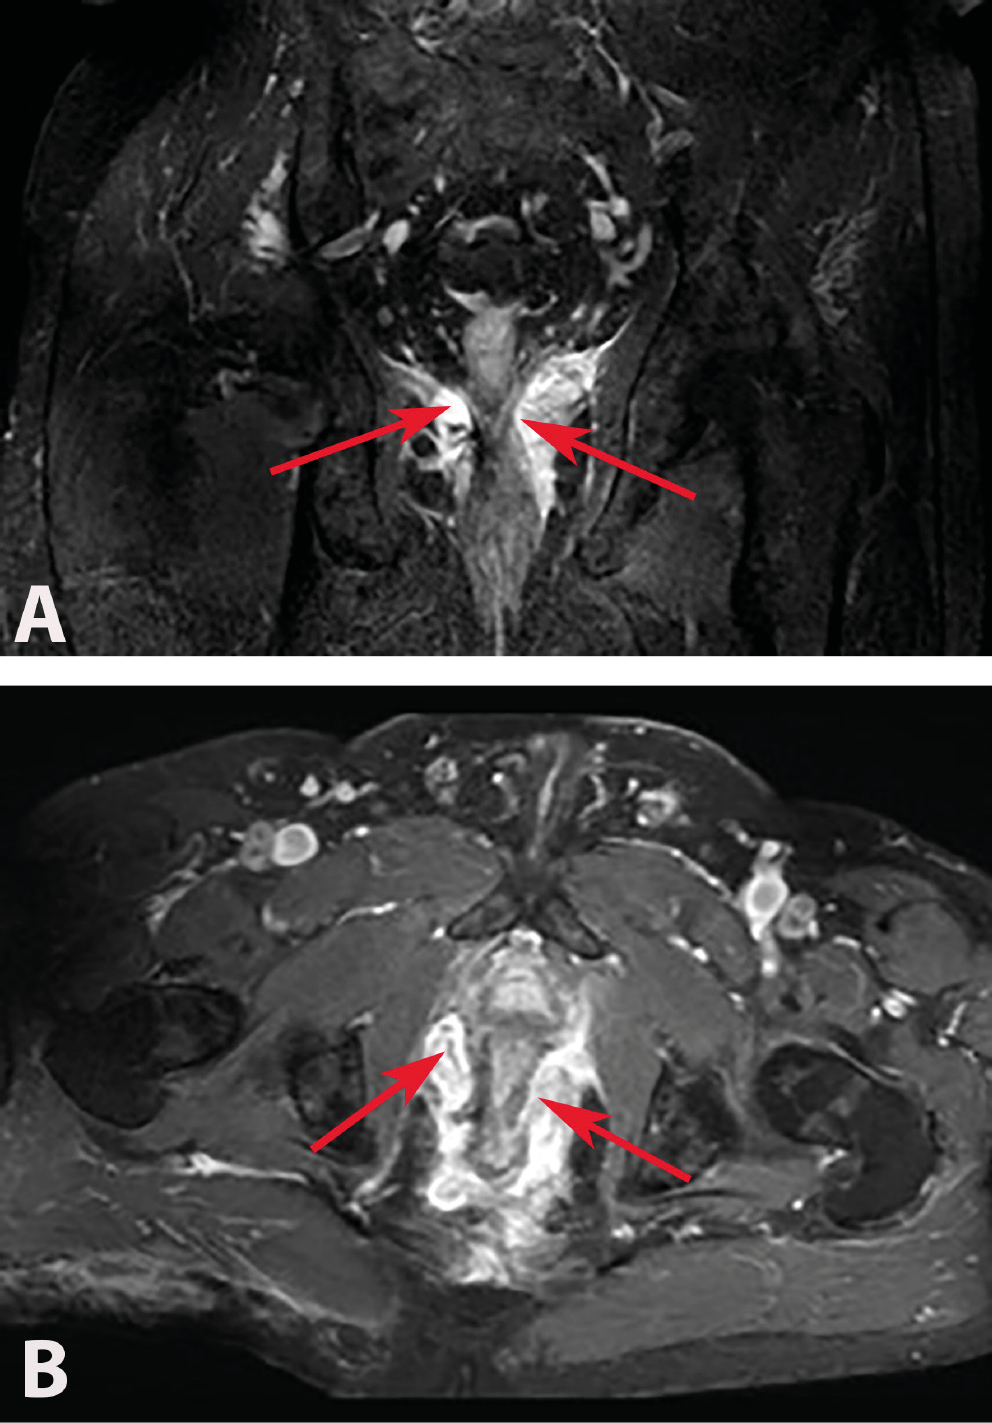

Of the 114 patients included in the study, 78 had complex chronic anal fistulas, and 36 had anorectal abscesses accompanied by anal fistulas. As a result of the MRIs performed in the anorectal abscess group, perianal abscesses were detected in 14 (58%) patients (Figure 2A,B), ischiorectal abscesses in 6 (25%) patients (Figure 3A,B) and intersphincteric abscesses in 4 (17%) patients (Figure 4). Suprasphincteric fistulas were observed in 3 patients, extrasphincteric fistulas were found in 2 patients, horseshoe fistulas were present in 2 patients (Figure 5A,B), and transsphincteric fistulas were observed in the remaining patients with complex fistulas. Thirteen patients had 2 external fistula ora and 4 patients had 3 external fistula ora. Eight patients in the fistula group had an abscess pouch associated with the fistula tract. These findings are consistent with the literature.